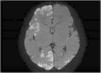

Recién nacida a término que presenta en su primer día de vida crisis convulsivas, consistentes en clonías en hemicuerpo izquierdo y desviación de la mirada. Presenta refractariedad a tratamiento anticonvulsivante habitual, cediendo con fenitoína. En RMNc se observan lesiones hiperintensas en difusión con afectación cortical extensa, parcheada y bilateral a nivel periventricular y subcortical (fig. 1). Se realiza EEG, estudio infeccioso, metabólico y oftalmológico normales.